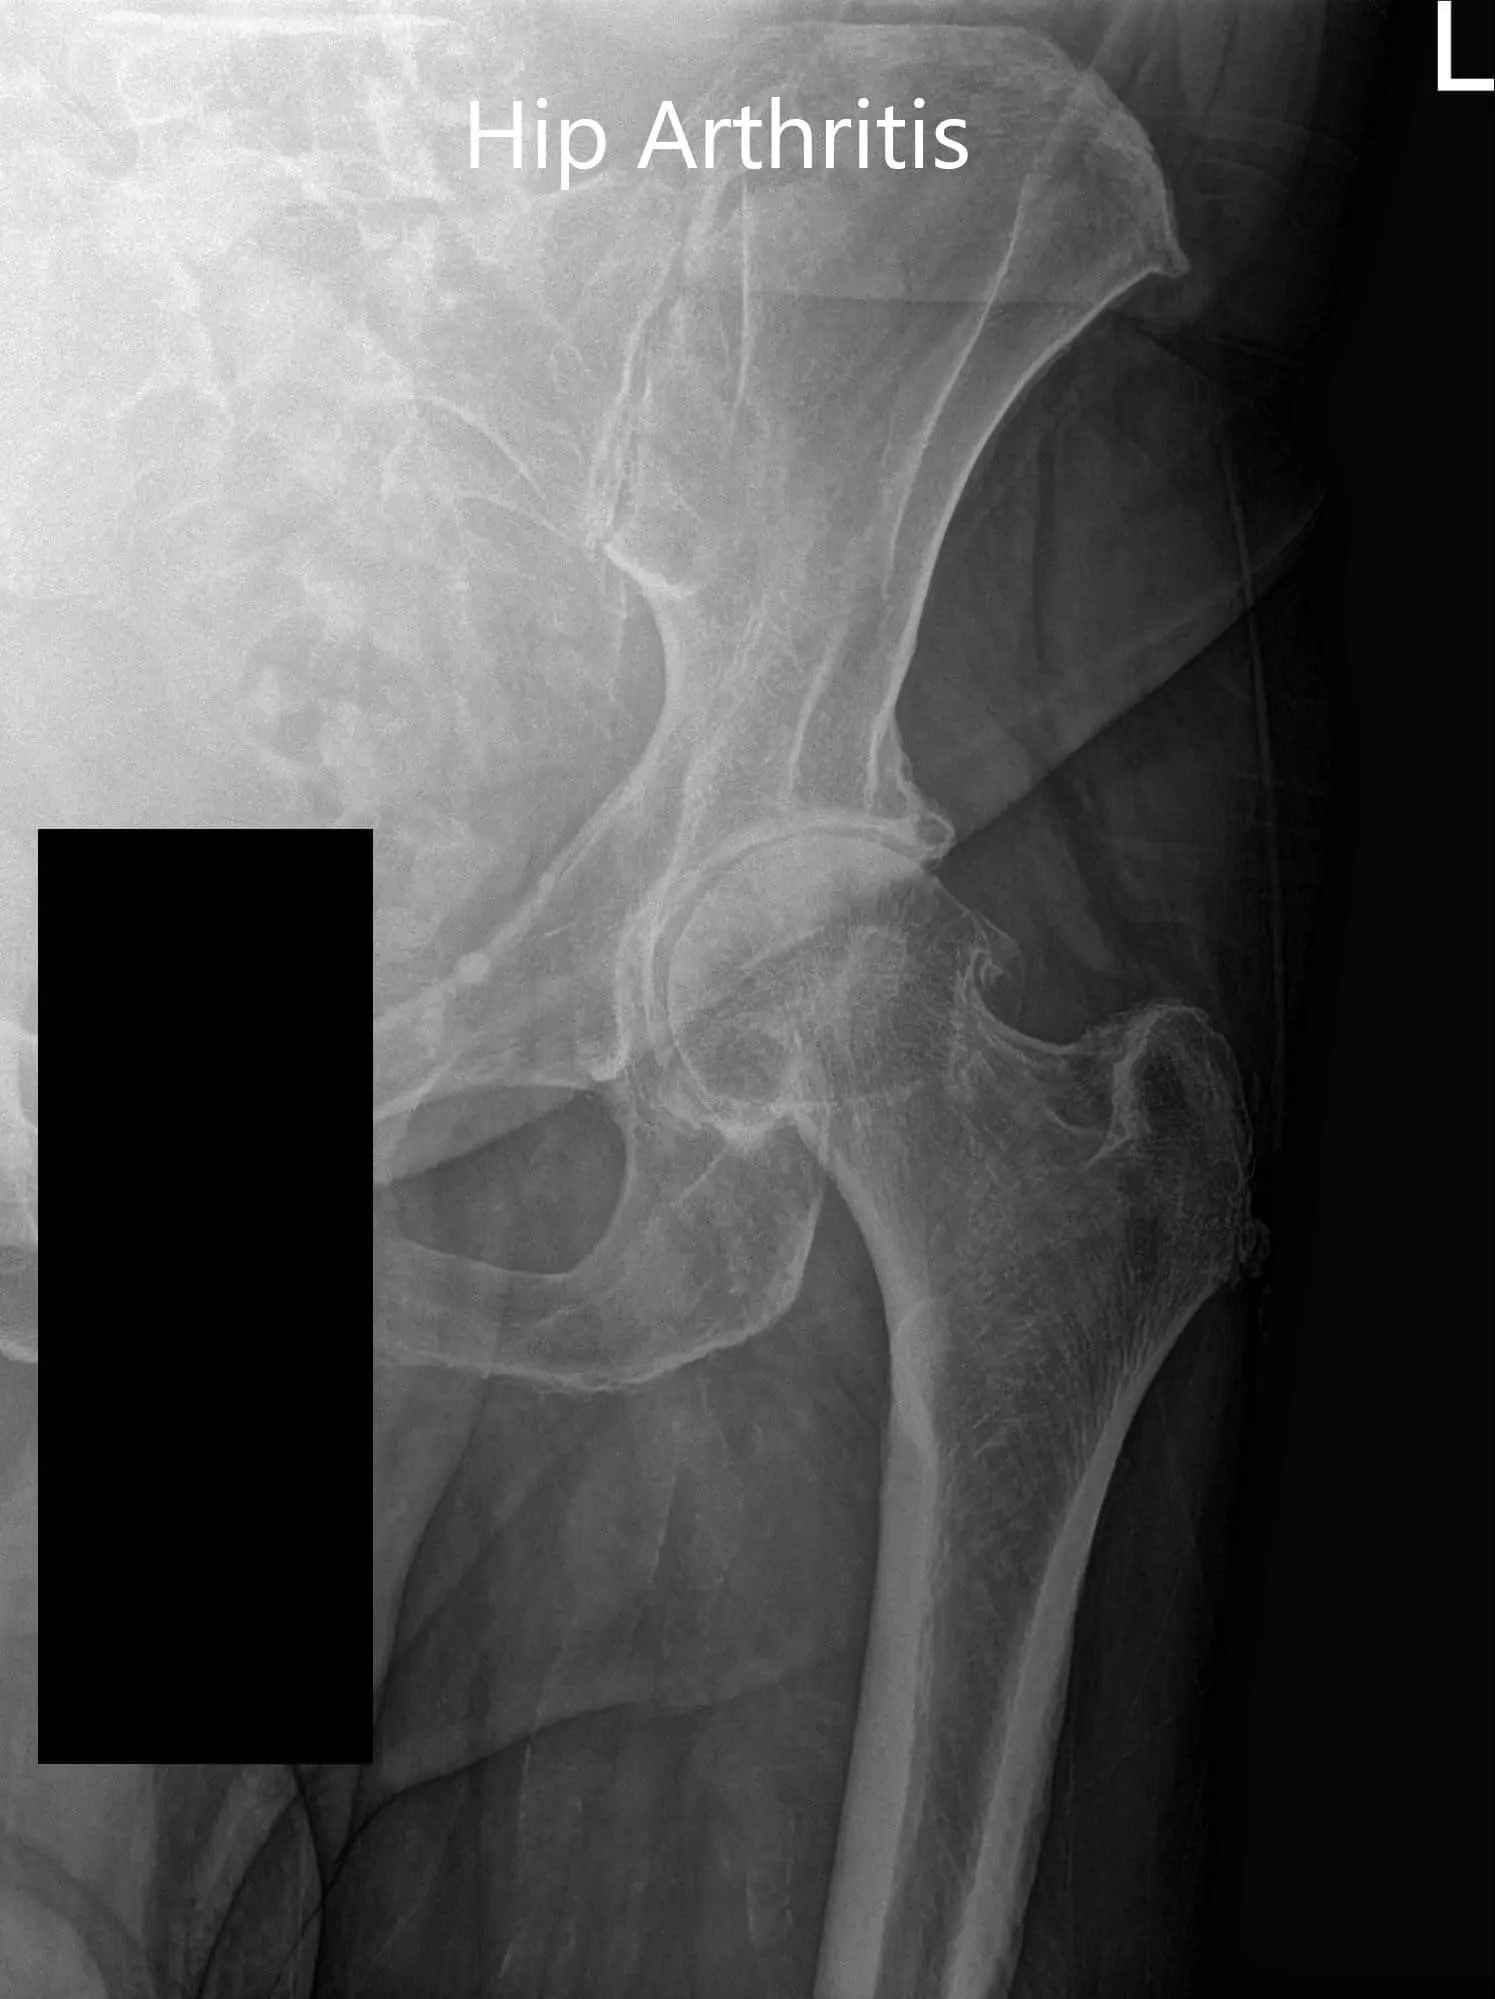

Imaging revealed severe osteoarthritis of the left hip. Considering, patients’ medical conditions and lifestyle limiting hip pain, she was advised left total hip replacement. Risks, benefits, and alternatives were discussed at length. She agreed to go ahead with the procedure.

Preoperative X-ray of the left hip showing AP and frog-legged lateral view

Preoperative X-ray of the left hip showing AP and frog-legged lateral view - img 2